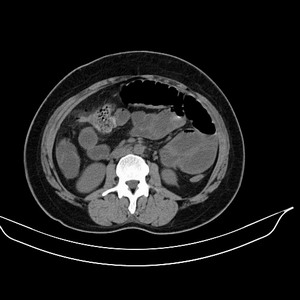

女 42岁 子宫肌瘤于外院术后两天,感腹胀。x线提示肠梗阻。

子宫肌瘤于外院术后两天,出现肠扭转梗阻,很明显。但右下腹部出现的线状高密度,是什么呢?有什么手术会有这样的物品呢?不会把电刀的导线遗留在腹腔吧!?

结果:术后纱布遗留,术后麻痹性肠梗阻肠梗阻

上面的图像是我们从手术室拿来的纱布做了个ct平扫,发现纱布里确实存在有一条致密影。后得知致密影是为防止手术时纱布遗留而设计。关腹时怀疑纱布遗留可做个床边透视或拍片可明确。